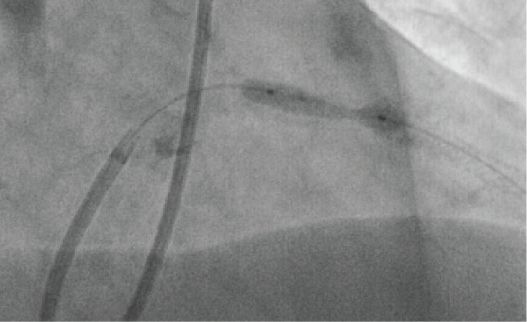

The first patient, a 65-year-old male, presented to our emergency department with unstable angina without troponin elevation for the first time in January 2015. A calcified culprit lesion in the Right Coronary Artery (RCA) was managed by stenting. Staged Percutaneous Coronary Intervention (PCI) of a significant proximal stenosis of the Left Anterior Descending (LAD) was scheduled for March 2015. During this procedure, two drug-eluting stents were implanted in a highly calcified and tight stenosis of the LAD (Figure 1). Significant residual stenosis was observed, which could not be resolved by high-pressure angioplasty at 26 atm with a non-compliant balloon catheter, or even at 35 atm with an ultra-high pressure balloon (OPN NC balloon, SIS Medical, Switzerland) (Figure 2). The stable patient was transferred the next day to a high-volume center for definitive treatment of the lesion by repeat angioplasty or alternatively rotablation of the implanted stent as a bail-out option. During this second procedure, a shorter ultra-high pressure balloon was inflated in the stent to optimize focussed pressure delivery to the resistant area. Pressure was increased slowly into the off-label range > 35 atm, as reported previously [1]. At 40 atm rupture of the balloon catheter occurred, as evidenced by an abrupt drop in pressure in the indeflator (device to in- and deflate PCI balloons). Unusually, the balloon itself remained inflated within the coronary artery, i.e. filled with contrast medium (Figure 3), whereas the rupture had obviously taken place in a more proximal part of the catheter. As the inflated balloon fully occluded the LAD, ST segment elevations were noted on the monitor ECG and the patient began to suffer from angina. When gentle pull was applied to remove the still inflated balloon from the coronary artery, the proximal shaft completely detached from the distal part at the rupture site (Figure 4 and Figure 5). An attempt to puncture the inflated balloon inside the LAD with the stiff end of a coronary wire that was advanced through a microcatheter failed. Removal of the detached and still partially inflated balloon from the calcified lesion was eventually achieved by "jailing" the remaining balloon shaft in the guiding catheter with another balloon inflated at high pressure inside the guide and then carefully retracting the catheter together with the balloon (Video 1). Total ischemia time until successful retrieval was 30 min. Patient recovery was uneventful and without residual wall motion abnormalities at discharge, although the complication led to a significant increase in necrosis markers and stent deployment was still suboptimal.

Figure 1: Right anterior oblique cranial projection showing suboptimally expanded stents in the proximal LAD. View Figure 1